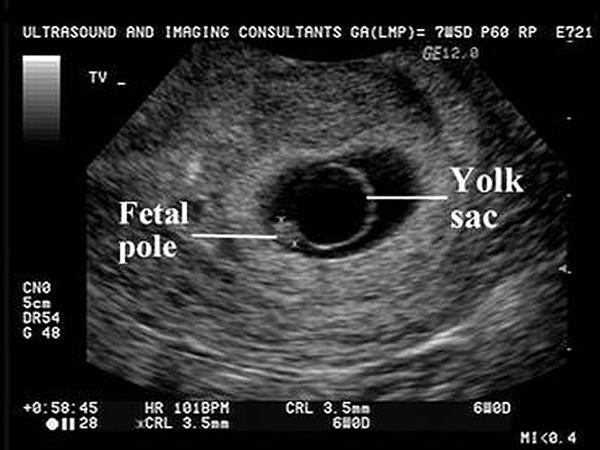

Hình ảnh túi thai là một phần quan trọng trong hành trình mang thai của người mẹ. Theo như kinh nghiệm dân gian, hình dáng của túi thai có thể dự đoán giới tính của thai nhi. Túi thai hình dài thường được cho là dấu hiệu cho biết mẹ đang mang bầu bé trai, trong khi túi thai hình tròn hoặc bầu dục thường được xem là dấu hiệu của bé gái.

Ngoài ra, chiều dài xương đùi của thai nhi cũng là yếu tố có thể giúp xác định giới tính. Thai nhi có hình dáng tròn thường liên quan đến các bé gái, trong khi thai nhi hình dáng dài lại thường là dấu hiệu của bé trai. Những thông tin này thường được các mẹ bầu truyền tai nhau từ nhiều thế hệ, tạo nên những câu chuyện thú vị quanh việc dự đoán giới tính.

Hình ảnh siêu âm thai luôn mang lại niềm vui và sự hồi hộp cho các bậc phụ huynh. Khi xem các bức ảnh siêu âm, các bậc cha mẹ có thể thấy những thay đổi nhỏ nhưng đáng yêu của thai nhi qua từng tuần. Chẳng hạn, ở tuần thứ 6, hình ảnh túi thai như một chiếc nòng nọc, và đến tuần thứ 7, các đặc điểm như ngón tay, ngón chân bắt đầu hình thành rõ nét hơn.